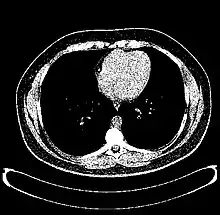

The Hounsfield scale (/ˈhaʊnzfiːld/ HOWNZ-feeld), named after Sir Godfrey Hounsfield, is a quantitative scale for describing radiodensity. It is frequently used in CT scans, where its value is also termed CT number.

Values for different body tissues and material

HU-based differentiation of material applies to medical-grade dual-energy CT scans but not to cone beam computed tomography (CBCT) scans, as CBCT scans provide unreliable HU readings.[4]

Values reported here are approximations. Different dynamics are reported from one study to another.

Exact HU dynamics can vary from one CT acquisition to another due to CT acquisition and reconstruction parameters (kV, filters, reconstruction algorithms, etc.). The use of contrast agents modifies HU as well in some body parts (mainly blood).

A practical application of this is in evaluation of tumors, where, for example, an adrenal tumor with a radiodensity of less than 10 HU is rather fatty in composition and almost certainly a benign adrenal adenoma.[28]